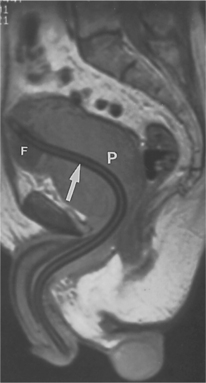

Uroflowmetry by itself is a screening modality, not diagnostic, because the urinary obstruction could be occurring at sites other than at the prostate gland. In addition, diagnostic ultrasound, magnetic resonance imaging (MRI), and abdominal radiographs may be used to evaluate the size and length of the urethra, the size and configuration of the prostate, and the bladder capacity (Fig. 19-4). The American Urological Association has also developed a self-administered screening tool used to determine the frequency and severity of urinary symptoms.

Figure 19-4 Magnetic resonance image (MRI) demonstrating benign nodular hyperplasia with enlargement of the prostate gland (P). The arrow is pointing to a Foley catheter in place. The inflated Foley balloon (F) indicates the level of the bladder neck. (From Grainger RG: Grainger & Allison’s diagnostic radiology: a textbook of medical imaging, ed 4, Philadelphia, 2001, Churchill Livingston.)